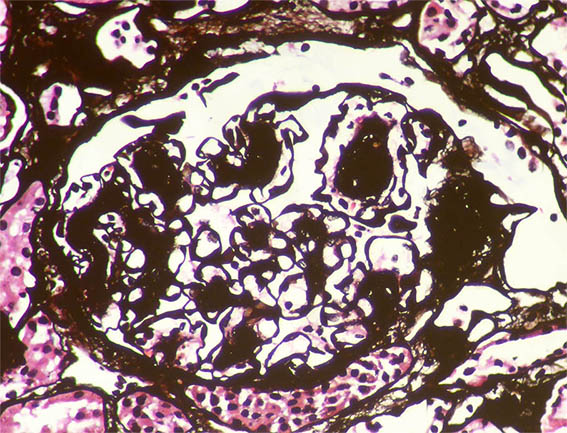

Figura 8. Plata-metenamina, X400.

Figura 9. Plata-metenamina, X400.